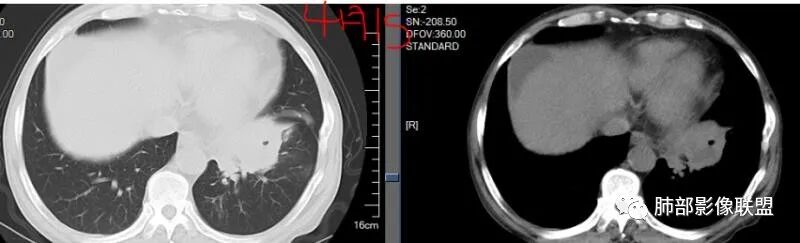

发一个金葡的对比一下

我这个也是金葡菌

3.金黄色葡萄球菌临床中毒症状明显,常寒颤高热起病,血源性感染者常有皮肤脓肿、伤口感染、蜂窝织炎、化脓性骨髓炎等等。病情变化快,影像进展迅速,短期内(如一两天内)迅速出现的有张力的菲薄气囊影,或多发成串分布的,尤具特征性!较之其他感染,短期内易出现脓胸。本例上述特征似乎不明显。

金葡应该也是血源性来源,因此也存在鉴别,区别在肝脏,肺克的血播是肝脏来源,金葡的血播可以各种来源,但是一般不会是肝脏来源,具体来说,金葡的SPE观察不那么典型,金葡可以形成更大的实变,肺克少一些,金葡的特征应该还是气囊,壁的张力更高,更薄,SPE似乎不明显,临床上皮肤软组织脓肿的有无,这个特征肺克应该不具有,但肺克一般有肝脓肿,没有的少见。